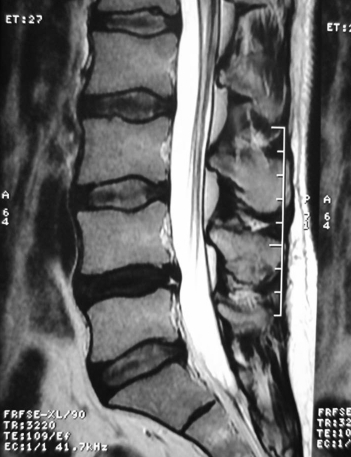

Lomber MRG - L4-L5 Disk Dejenerasyonu ve HIZ

Resim 1: Hastanın T2 ağırlıklı lomber MRG incelemesinde L4-L5 diskinin dejenerasyon nedeniyle su içeriğinin azalmasına bağlı olarak siyahlaştığı görülmektedir. Bu mesafede posterior anulus fibrozusta noktavari bir parlama şeklinde görülen yüksek sinyal intensitesi (HIZ: high intensity zone) izlenmektedir ve bir anüler yırtıkla uyumludur.